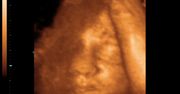

Zdjęcia płodu

Zdjęcia płodu - twarze